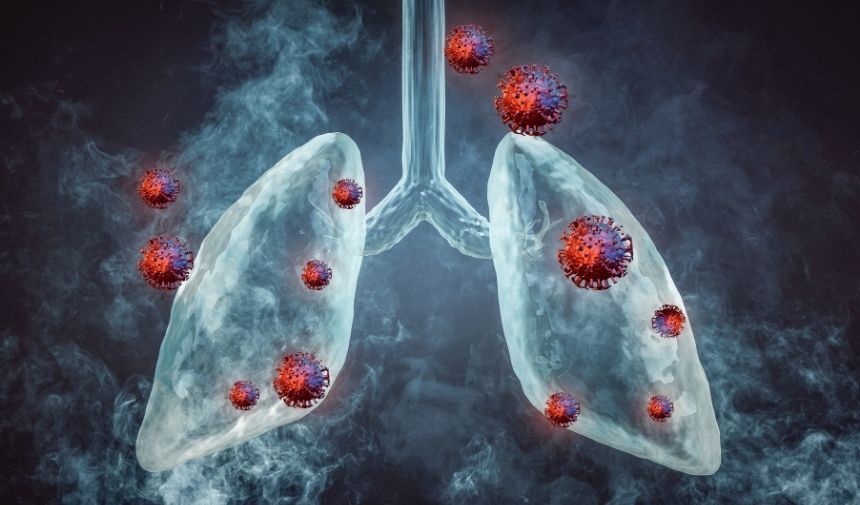

2019'da ABD'de ilk kez görülen bu hastalık, son zamanlarda ülkemizde de görülmeye başlamıştır.

EVALI Belirtileri:

- Balgam

- Öksürük

- Nefes darlığı

- Ateş

- Bulantı

- Kusma

- İshal

- Kilo kaybı

- İştahsızlık

EVALI Tanısı:

Son 90 gün içinde elektronik sigara veya türevlerini kullanan kişilerde, yukarıdaki belirtiler ve akciğer grafisinde her iki tarafta zatürre görünümü varsa EVALI tanısı konulabilir.

EVALI'nin Tehlikeleri:

- EVALI, kalp ve damar hastalıklarına yakalanma riskini sigara kadar yüksektir.

- Boşaltım ve sindirim sistemlerinde geri dönüşü olmayan sağlık sorunlarına neden olabilir.

- Kısırlığa yol açabilir.

Elektronik Sigaranın Zararları:

- EVALI'nin yanı sıra elektronik sigaranın birçok zararı vardır.

- Nikotin içeren elektronik sigaralar, kalp ve damar hastalıklarına yakalanma riskini artırır.

- Elektronik sigara kullanımı, idrar yolları, bağırsak ve midede ciddi sorunlara yol açabilir.

- Elektronik sigara, ağızda kuruluk, mide ekşimesi ve küsme gibi şikâyetlere neden olabilir.

- Elektronik sigara, tıpkı sigara gibi kısırlığa yol açabilir.